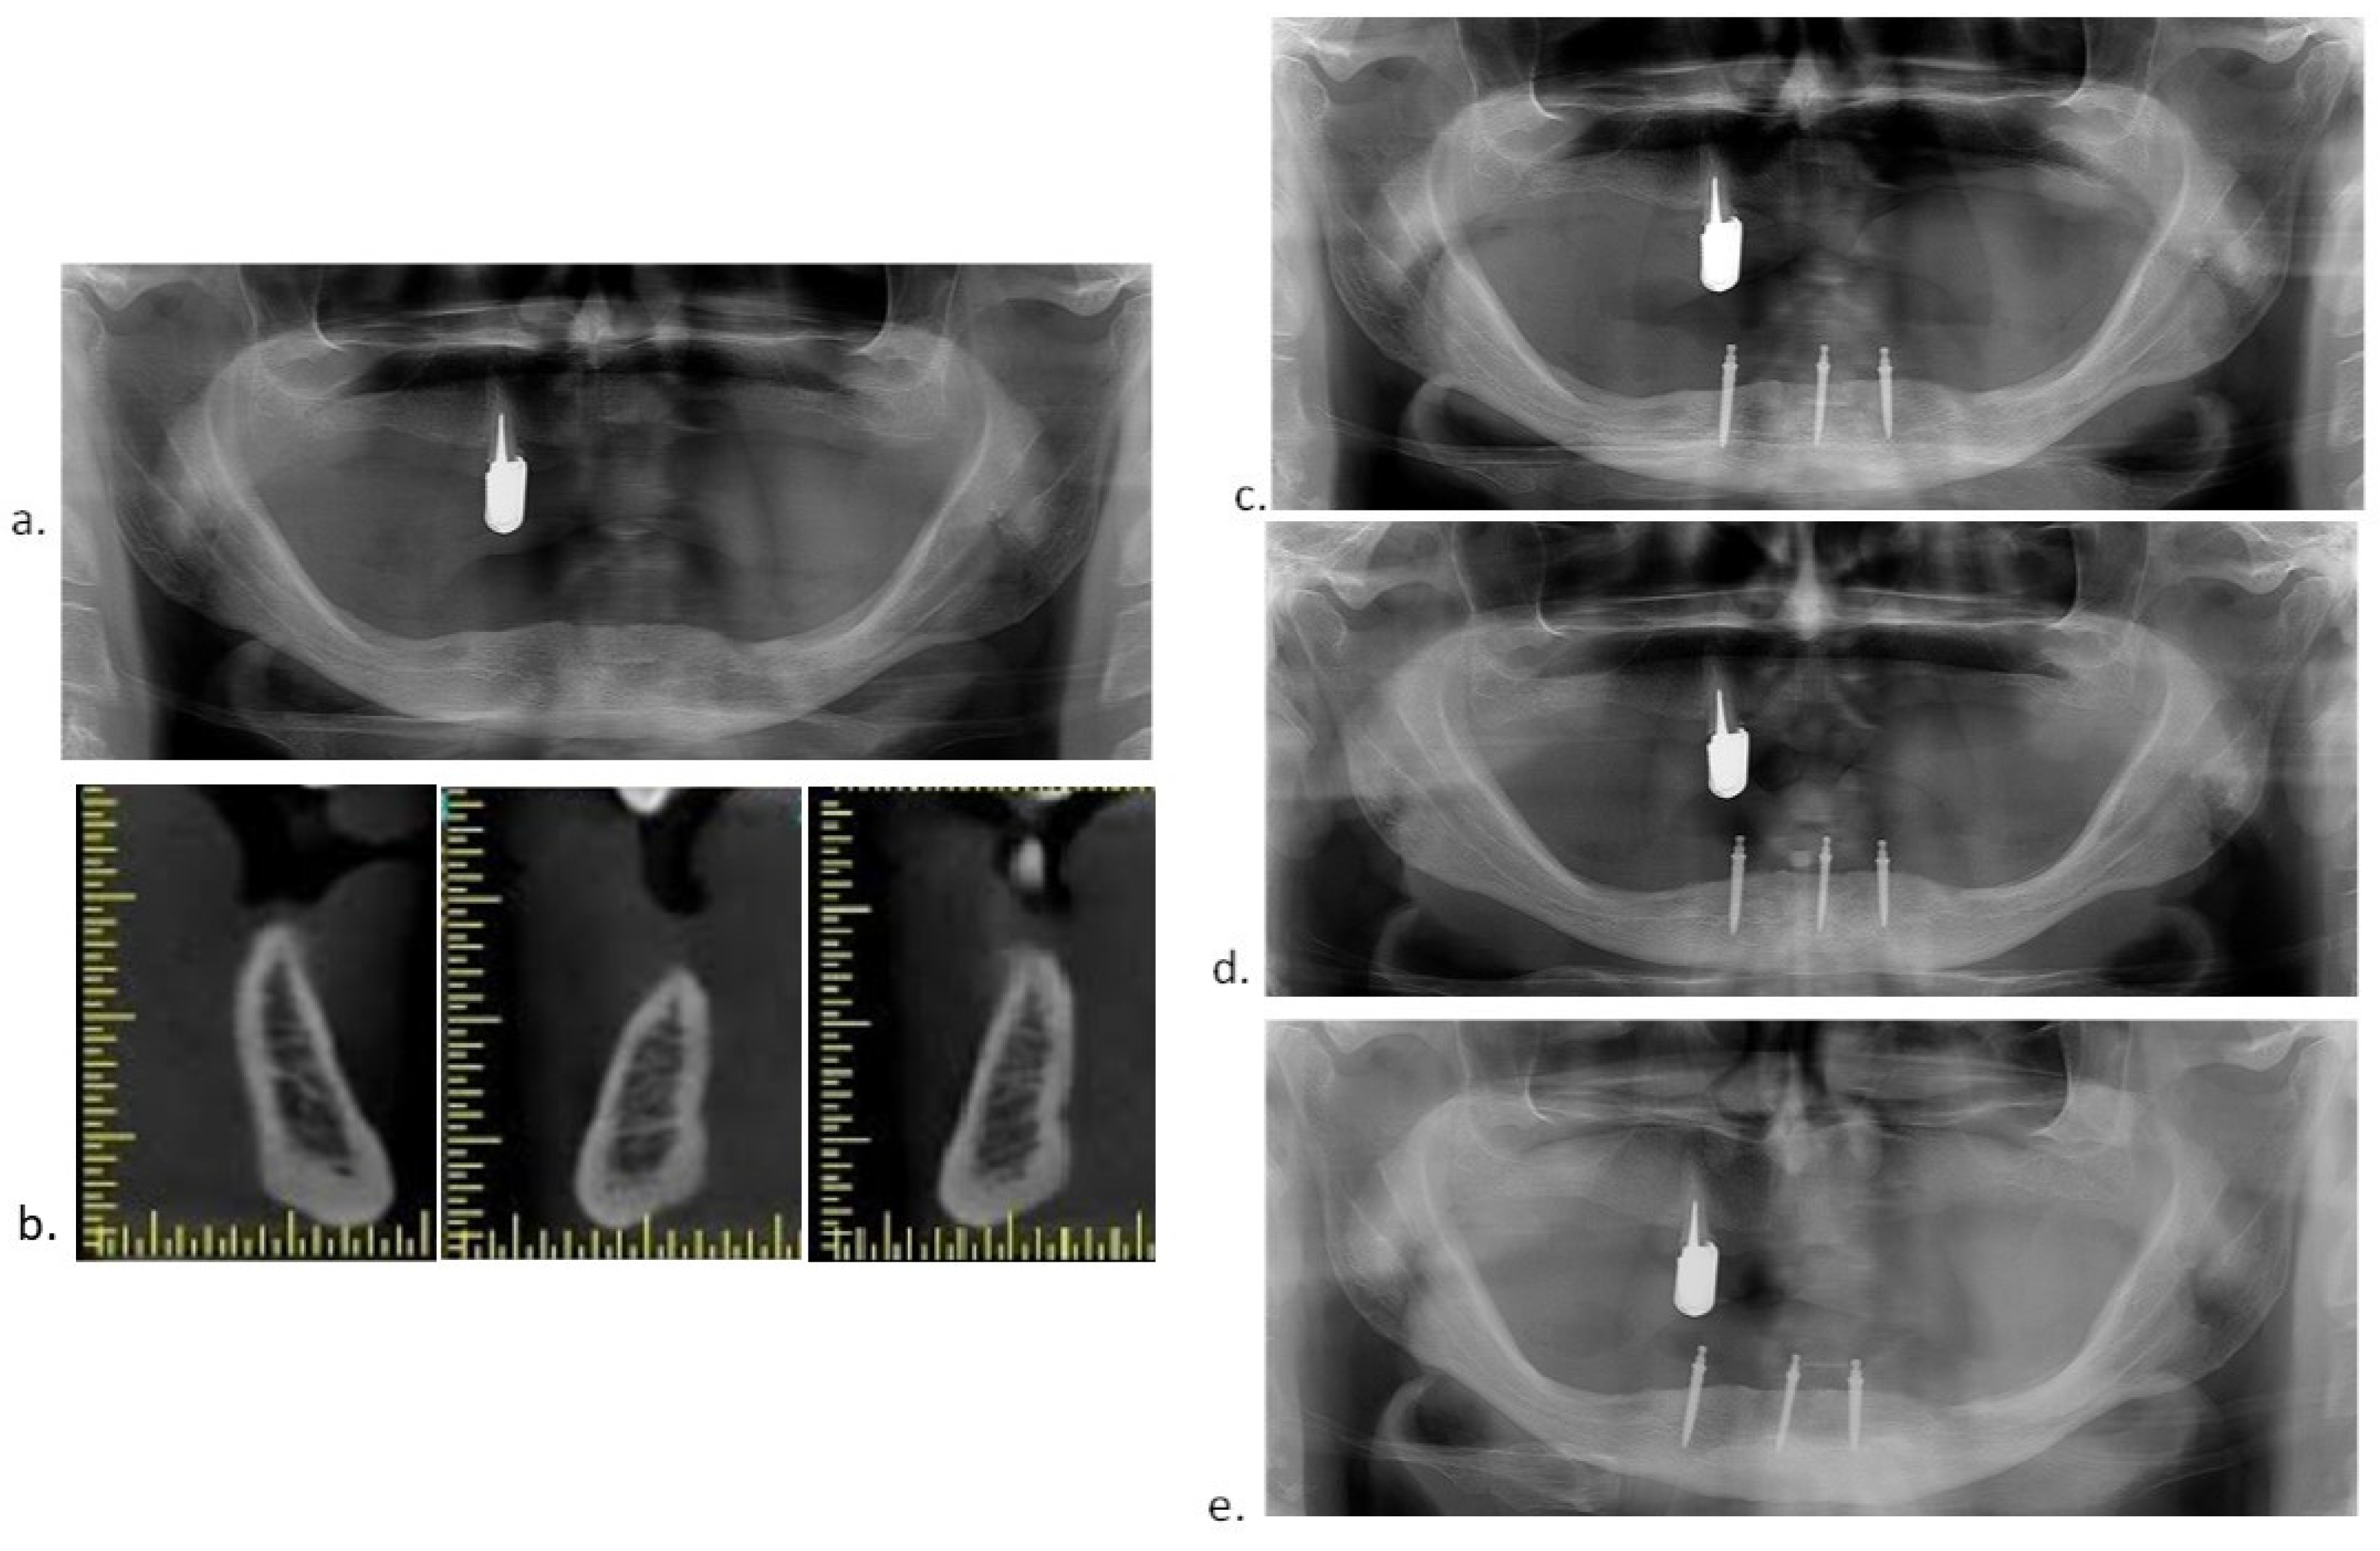

2.4. Surgical Procedures

2.5. Prosthodontic Protocol

2.6. Radiographic Evaluation